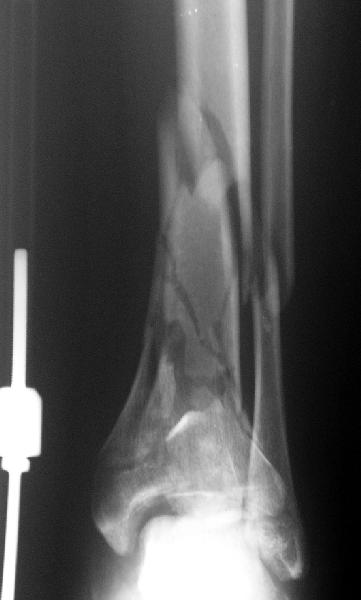

Re: Открытый оскольчатый внутрисуставной перелом дистального отдела большеберцовой кости

Вот что получилось

7.jpg

27KB (28411 bytes)